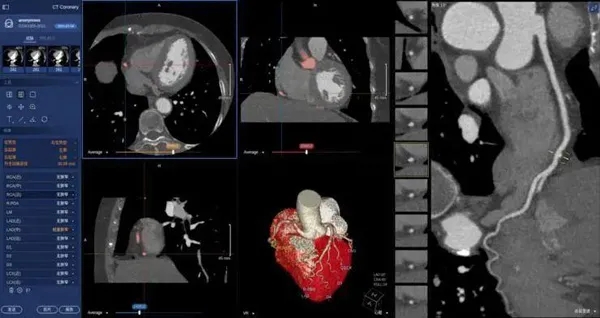

在醫(yī)學(xué)領(lǐng)域,機器視覺主要用于醫(yī)學(xué)輔助診斷。首先采集核磁共振、超聲波、激光、X射線、γ射線等對人體檢查記錄的圖像,再利用數(shù)字圖像處理技術(shù)、信息融合技術(shù)對這些醫(yī)學(xué)圖像進行分析、描述和識別,最后得出相關(guān)信息,對輔助醫(yī)生診斷人體病源大小、形狀和異常,并進行有效治療發(fā)揮了重要的作用。不同醫(yī)學(xué)影像設(shè)備得到的是不同特性的生物組織圖像,如X射線反映的是骨骼組織,核磁共振影像反映的是有機組織圖像,而醫(yī)生往往需要考慮骨骼有機組織的關(guān)系,因而需要利用數(shù)字圖像處理技術(shù)將兩種圖像適當?shù)丿B加起來,以便于醫(yī)學(xué)分析。